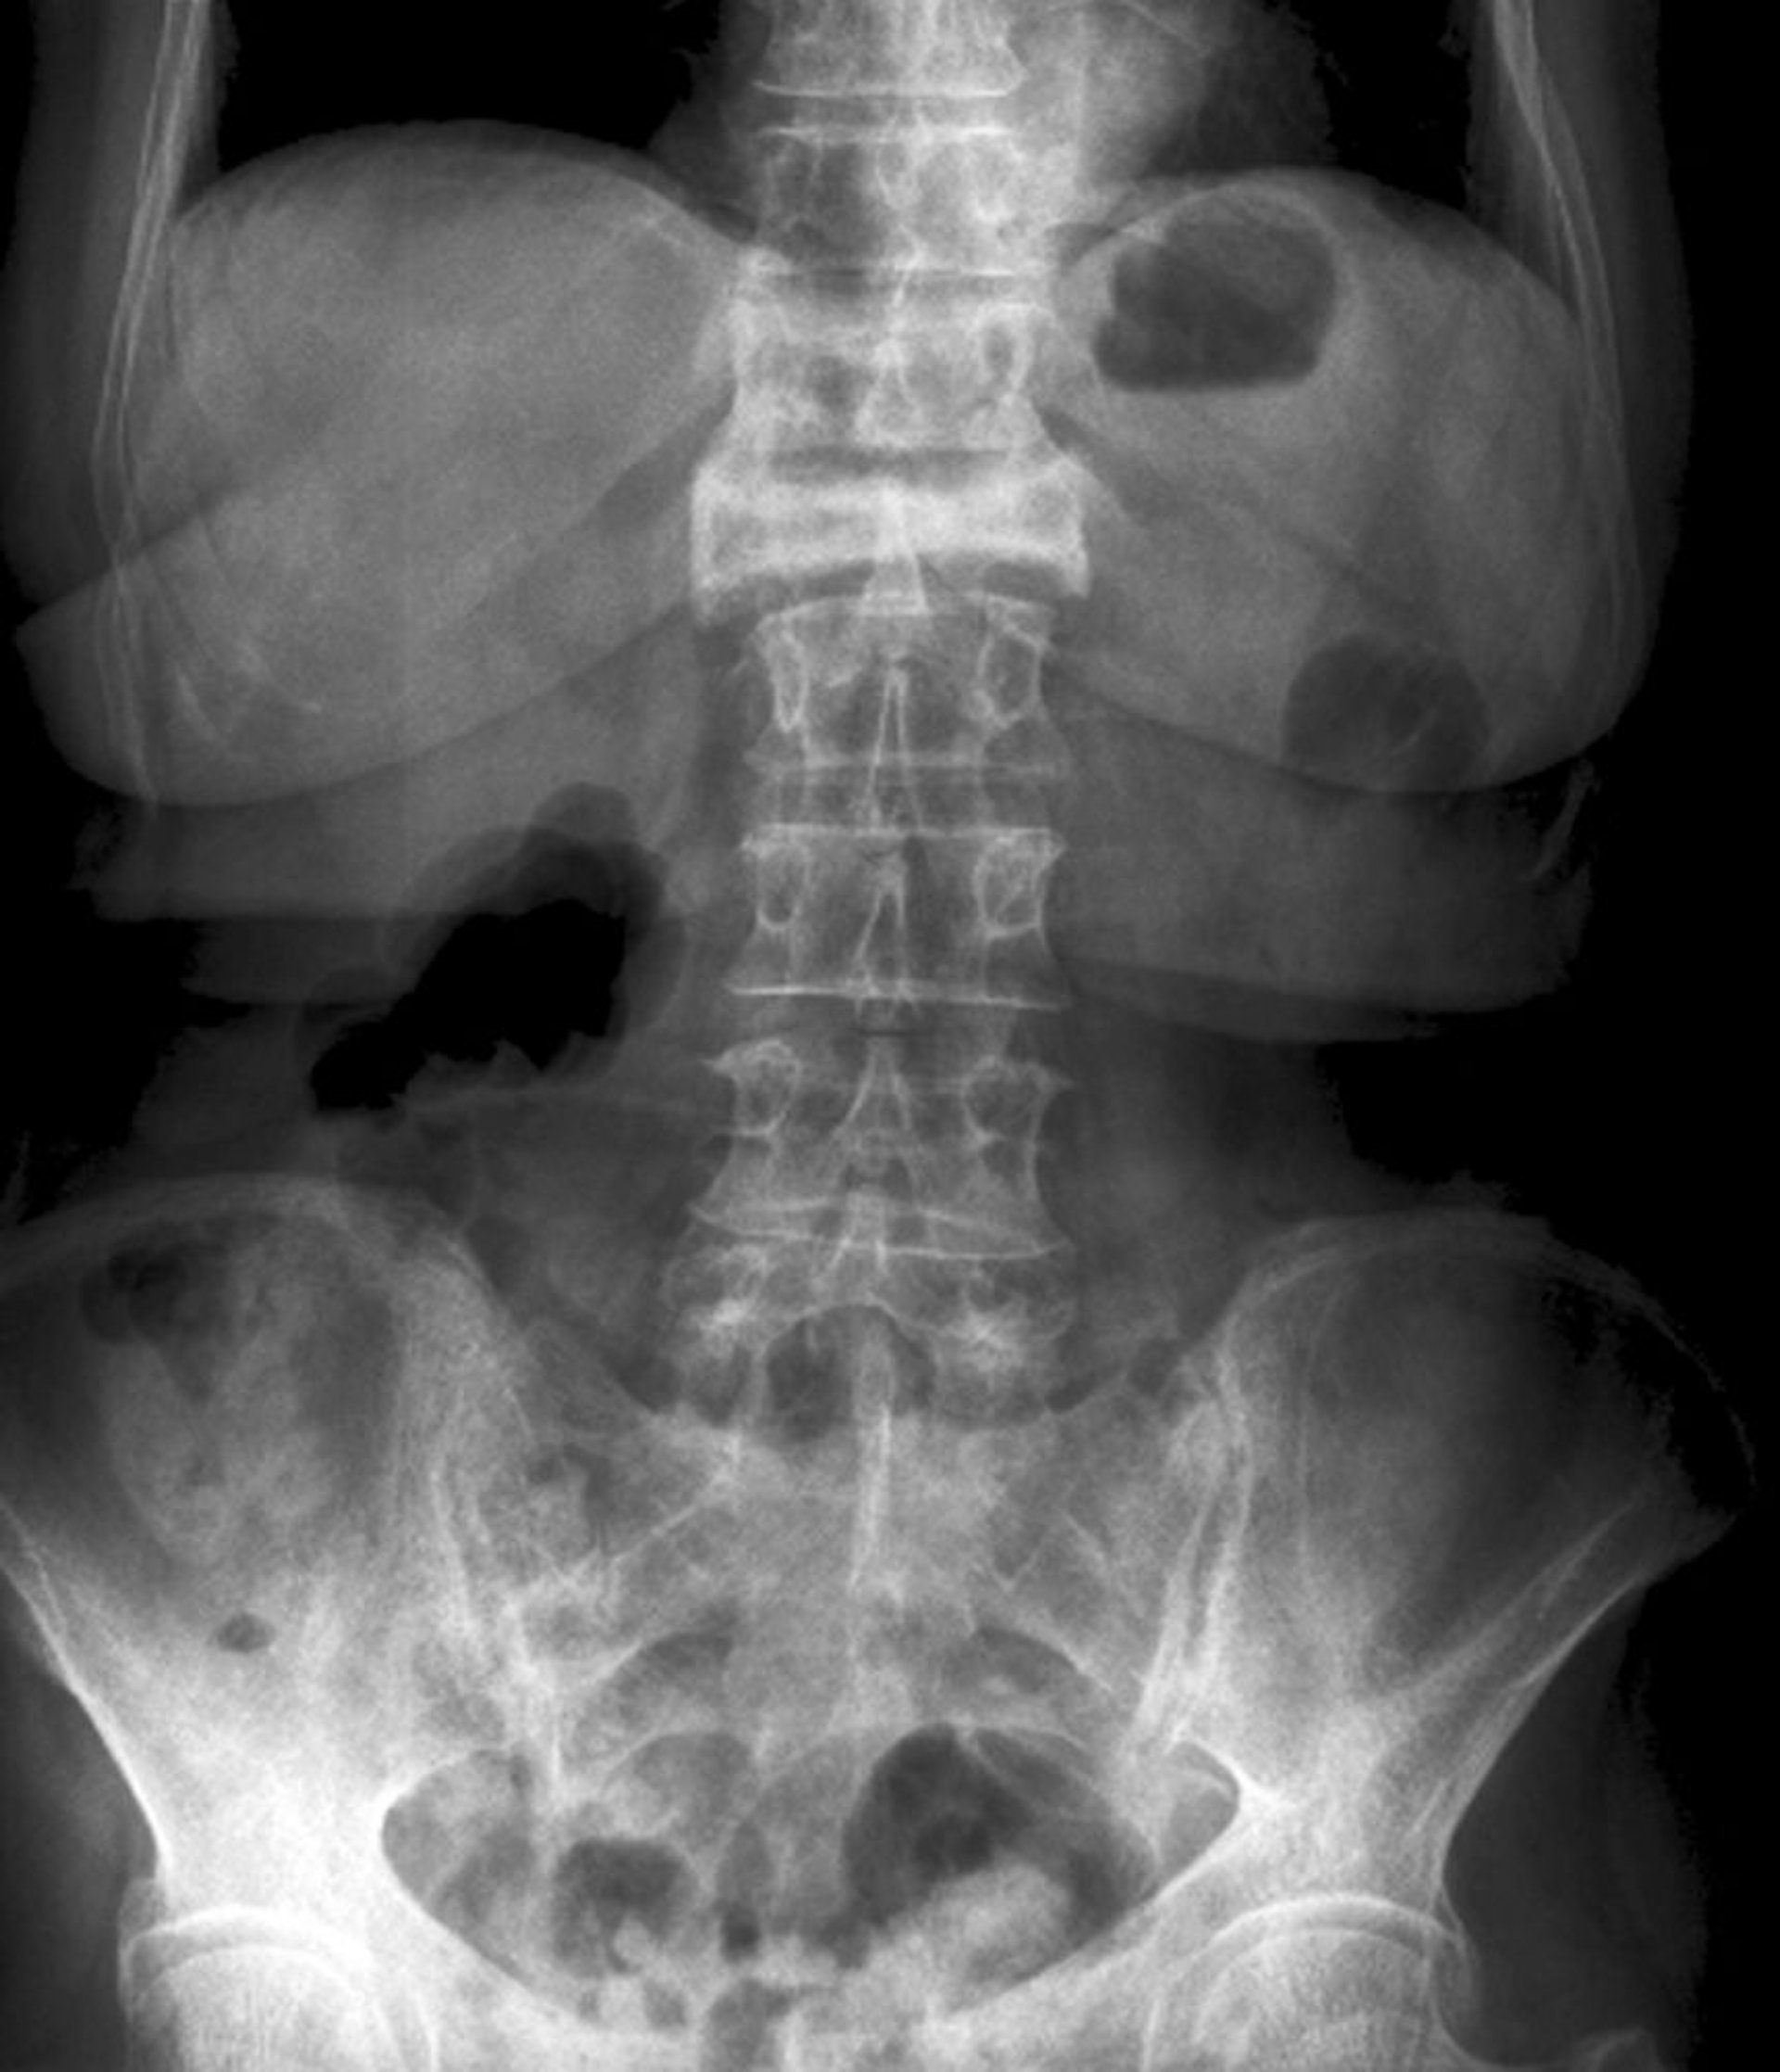

Incidenza antero-posteriore di una grave frattura da compressione

Questa frattura da compressione della prima vertebra lombare è visibile sulla vista anteroposteriore come una grave perdita di altezza e aumento della radiodensità.